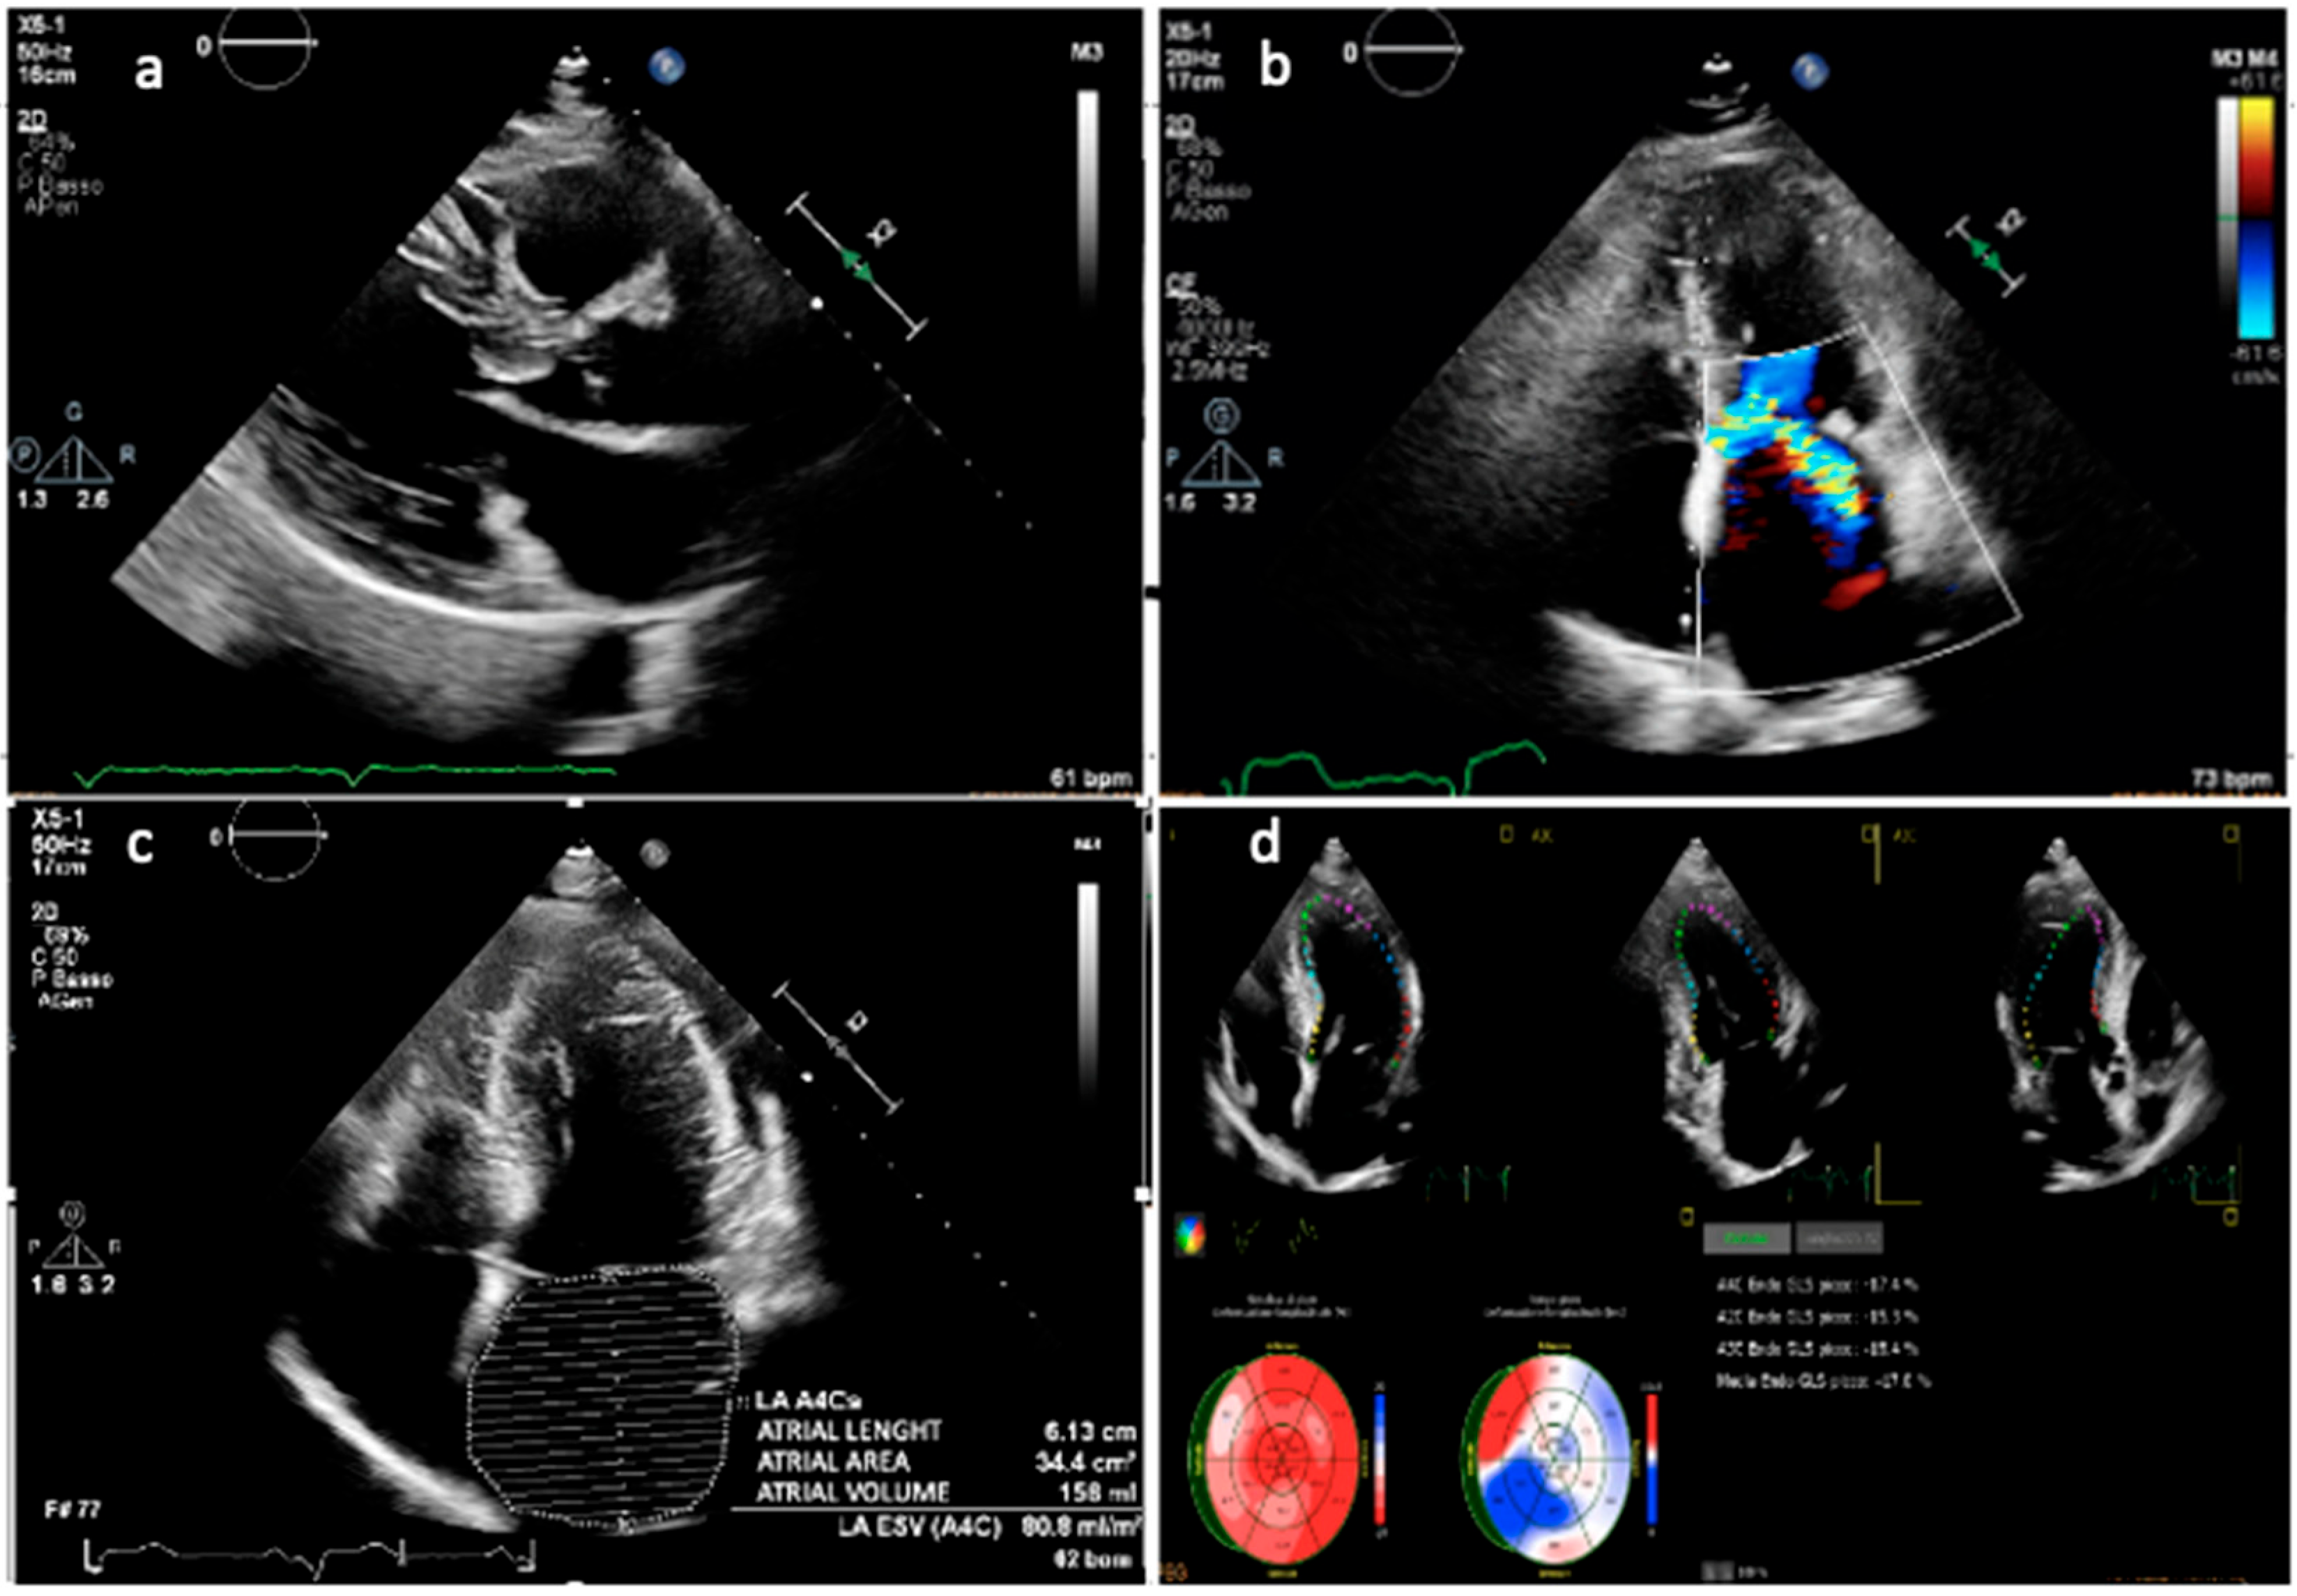

4.4. Left Atrial Enlargement

4.5. Diastolic Function

4.6. Strain Imaging